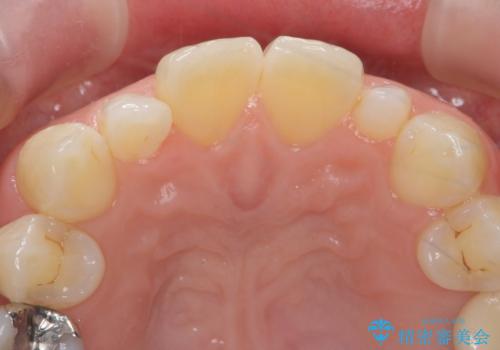

隣の前歯が小さいため、4本被せてバランスをとりました。

歯の向きは悪くなかったため、神経は取らずに治療しました。

- 前歯が大きいのを揃えたいとのことでした。

少し削って長さを短くして様子を見ましたが、どうしても気になるとのことでした。